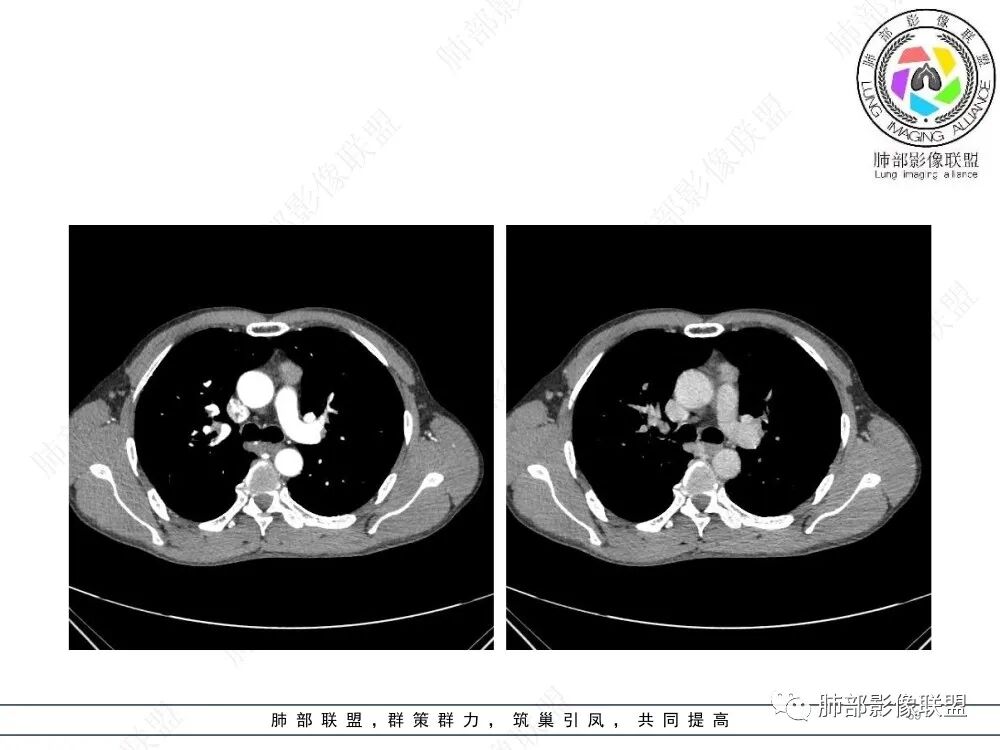

1、临床特点:47岁男性,咳嗽咳痰1年余。实验室检查无特殊。

2、影像特点:前纵隔偏左侧软组织影,密度相对均匀,未见明显包膜钙化及实质内钙化,局部边缘浅分叶,周围脂肪间隙密度增高、浑浊,未见侵犯大血管、未见纵隔内淋巴结转移、未见侵犯心包内结构、未见胸膜转移结节、未见肿块沿着纵隔胸膜蔓延,未见胸腔积液。增强后动脉期不均匀强化,未见明显纤维分隔。

3、 病 例 小 结:40岁以上,前纵隔偏侧性生长的肿块,常规考虑胸腺瘤。难点就在于胸腺瘤的分型。但是对于前纵隔占位影像诊断的关键在于区分胸腺囊肿、胸腺瘤、胸腺癌及其他恶性肿瘤。至于胸腺瘤,主要在于判断有无侵袭性。

胸腺瘤(thymoma)是最常见的前上纵隔原发性肿瘤,约占成人所有纵隔肿瘤的20%~40%,它起源于胸腺上皮,但不包括起源于生殖细胞、淋巴细胞、神经内分泌细胞及脂肪组织的肿瘤。绝大多数胸腺瘤位于前纵隔,附着于心包,与纵隔内大血管关系密切,少数发生在纵隔以外部位,如胸膜、心膈角、肺实质内、肺门或颈部。胸腺瘤生长缓慢,多为良性,包膜完整,但临床上有潜在的侵袭性,易浸润周围组织和器官。胸腺瘤与自身免疫紊乱密切相关,常伴有重症肌无力(mysasthenia gravis,MG)、各类粒细胞减少症、红细胞发育不良、低丙种球蛋白血症、胶原血管病等副瘤综合征(paraneoplastic syndromes)。国外文献显示胸腺瘤在人群中的年发病率是0.15/10万,男女比例为1:1,发病高峰年龄在40~50岁。胸腺瘤伴发重症肌无力的发生率约为10%~46%,多在30~40岁。儿童胸腺瘤罕见,但恶性程度更高。胸腺瘤的发病机制目前尚不清楚。有学者认为患者既往有放射治疗和EB病毒感染史可能与胸腺瘤有关。